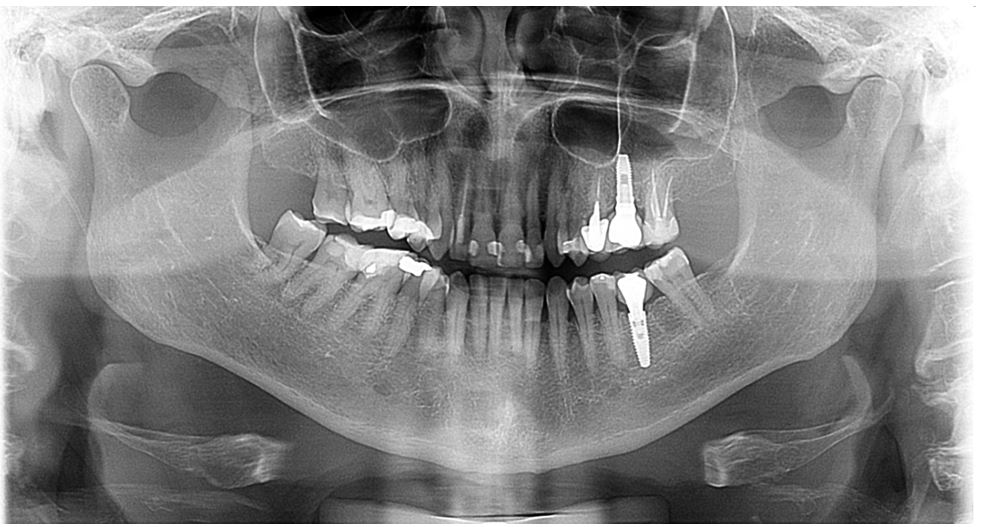

Implantes e Prótese Protocolo

Implantes Dentários e Prótese Protocolo em Bragança Paulista: A Solução Definitiva para dentes fixos

A Prótese Protocolo é uma reabilitação completa de uma arcada inteira (superior ou inferior) fixada sobre 4 a 6 implantes de titânio. Diferente da dentadura comum, ela não possui o “céu da boca” e não se movimenta. Ela é parafusada sobre os implantes pelo Dr. Marcos Scaranello, o que garante estabilidade total. Isso permite que o paciente volte a comer qualquer tipo de alimento — desde um churrasco até uma maçã — com a mesma força e segurança de quem possui dentes naturais.

A Tecnologia da Cirurgia Guiada na Ortoimplan Bragança Paulista

Para tornar o processo mais seguro e confortável, utilizamos a cirurgia guiada por computador. Através de um tomografia e um escaneamento intraoral, o Dr. Marcos planeja a posição exata de cada implante antes mesmo da cirurgia. Isso reduz o tempo de cadeira, minimiza o sangramento e, em muitos casos, elimina a necessidade de cortes extensos e pontos, proporcionando um pós-operatório muito mais tranquilo do que as técnicas convencionais.